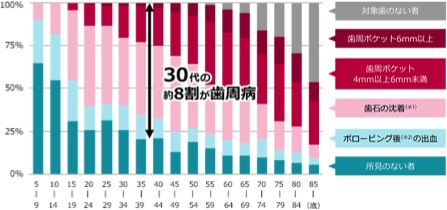

やってますねー。出血するという軽度なものから、もうかなり重症というところを含めて、日本人の「30代の8割が歯周病」という報告が出ています。

日本では30代以上の8割、5人に4人ですよ。かなり高確率のロシアンルーレット状態。